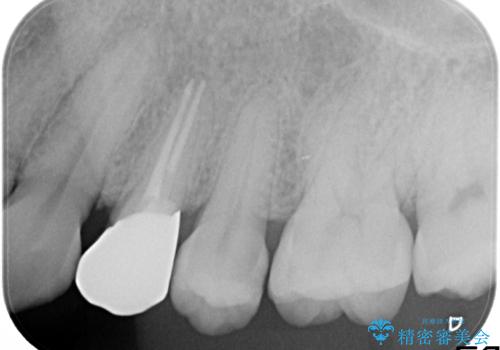

大きな虫歯で崩壊した歯の修復

- 虫歯が深かったため、根管治療を行い、土台を立て直しかぶせ物を製作します。

虫歯で奥歯が真っ黒になり崩壊していましたが、悪い部分を完全に取り除き、丁寧に修復することでまた長く機能させることができます。

かぶせ物のの種類:Bellezza